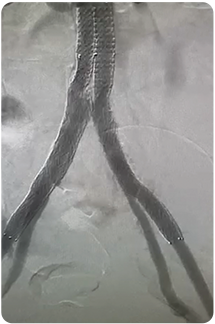

5 Fr Radial Access for Bilateral Iliac Artery Stenting Using the Surmodics Sublime™ 120 cm Guide Sheath

Robert Minor, MD

A woman in her early 60s with a medical history of smoking (former), statin intolerance, and coronary artery disease presented with severe right-greater-than-left buttock and thigh claudication and inability to walk one block. Ankle-brachial index (ABI) showed right ABI of 0.73 falling to 0.59 with exercise, and left ABI of 1.0 falling to 0.85 with exercise.